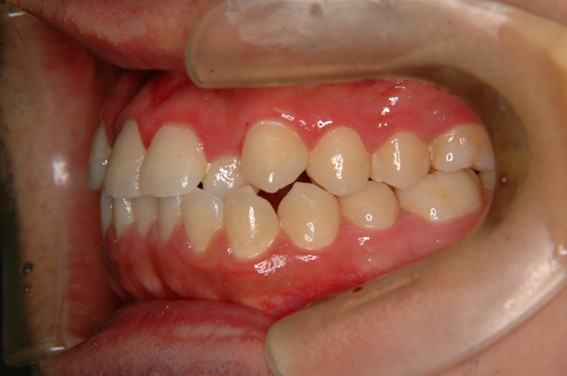

| 主訴 | 前歯が逆に噛んでいる。 |

| 治療内容 | 表側ワイヤー矯正、ジルコニア補綴を行いました。 |

| 治療費 | ワイヤー矯正660,000円(税込) ジルコニア176,000円(88,000円×2歯)(税込) |

骨格性Ⅲ級・前歯部反対咬合の症例でした。反対咬合のまま治療していた前歯のサイズ不調和を、表側ワイヤー矯正とプロビジョナルクラウンで調整。正中を整え、犬歯・臼歯ともⅠ級、適切なオーバージェット(上下前歯の前後的な距離)・オーバーバイト(上下前歯の垂直的な重なり)に仕上げました。